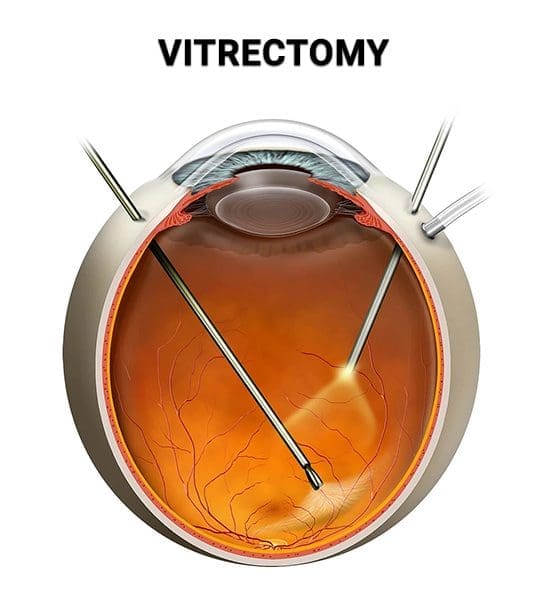

أطباء العينية

74 listings